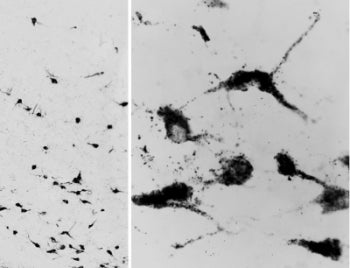

Oxytocin Antibody